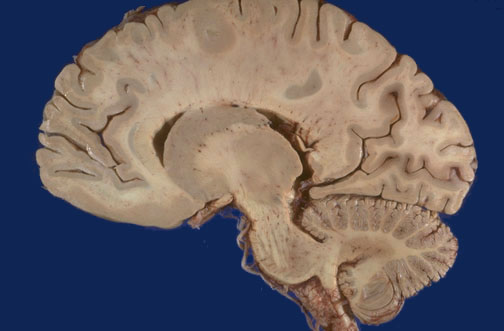

Identify the following regions of the brain on sagittal section by clicking in the image below:

Caudate nucleus - Thalamus - Pons - Cerebellum